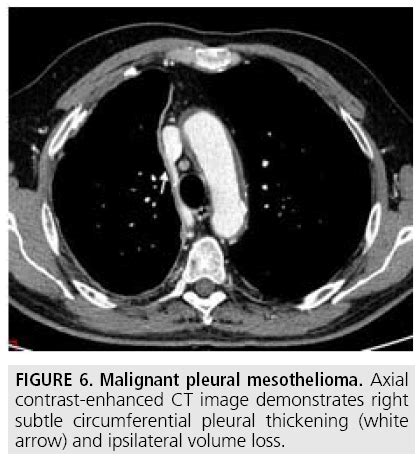

Symptoms of pleural and peritoneal mesothelioma typically appear in stages 3 and 4. You may need to have. Pleural mesothelioma occurs in about 2,000 people in the united states every year. Pleural mesothelioma originates in the lining of the lungs. Pleural mesothelioma affects the lung cavity, or pleura. The pleurae are serous membranes, which mean they secrete a lubricating fluid, called serous fluid. This is the most common type of mesothelioma. Complementary to contrast enhanced ct. Mesothelioma is a type of cancer that develops from the thin layer of tissue that covers many of the internal organs (known as the mesothelium). Malignant pleural mesothelioma is cancer of the lining of the lungs (pleura) caused by asbestos exposure. A malignant mesothelioma originating from cells of the pleura (the thin layer of mesothelium lining the lungs). Ct scans are approximately 90% sensitive for detecting pleural malignant mesothelioma. Pleural mesothelioma is a cancer of the pleura, the lining of the lungs.

The most common form of the disease, accounting for roughly 70% of cases, and occurs in the lining of the lung known as the pleura. This is the most common type of mesothelioma. Pleural mesothelioma is the most common form of this cancer and affects the lining of the lungs. Pleural mesothelioma (mesothelioma of the chest) has symptoms that include mesothelioma can cause fluid to build up around the pleura (called pleural effusion) or in the tummy (called peritoneal. Most people with pleural mesothelioma note shortness of breath and chest pain. Pleural mesothelioma is the most common type of mesothelioma, accounting for about 75 percent sometimes pleural mesothelioma spreads (metastasizes) and affects your outer chest wall, lymph. Pleural mesothelioma should be considered in any patient with a persistent undiagnosed exudate, especially if there is a history of exposure to asbestos, chest pain, a rindlike. Ct scans are approximately 90% sensitive for detecting pleural malignant mesothelioma.